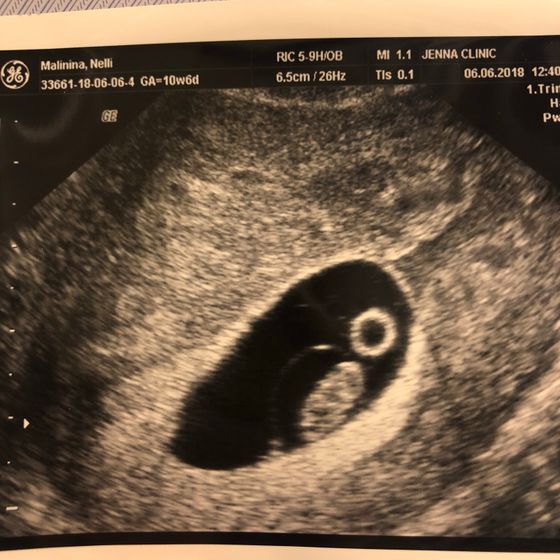

Сегодня была на плановом узи. Эмбрион уже визуализируется.

Сердечко бьется, 156 ударов в минуту.

Все у нас хорошо ? Можно вставать на учет в жк.